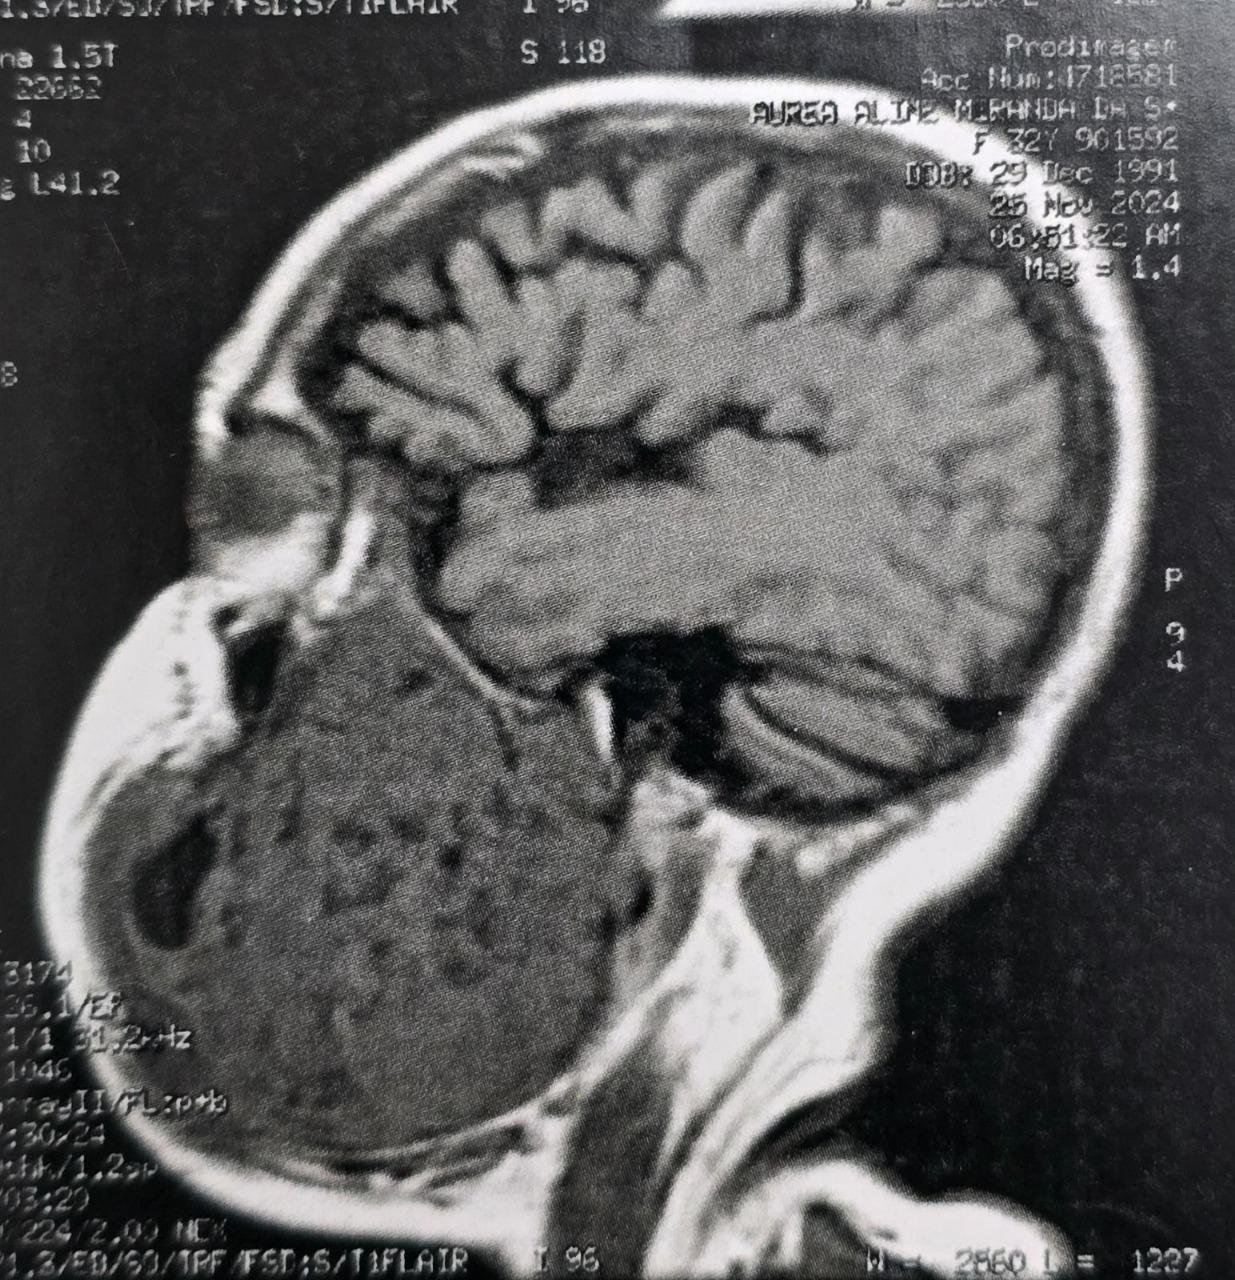

O tumor, diagnosticado como um ameloblastoma agressivo, comprometia aproximadamente 50% da mandíbula esquerda da paciente, provocando deformidade facial severa, além de grandes dificuldades para se alimentar e se comunicar. Natural do estado do Pará, a paciente convivia com o problema há oito anos e chegou a perder 30 quilos nos últimos meses.

A cirurgia mobilizou médicos altamente especializados das áreas de bucomaxilofacial, microcirurgia de cabeça e pescoço, além de cirurgia plástica. De acordo com o cirurgião bucomaxilofacial Flávio Fayad, o planejamento do procedimento envolveu exames detalhados e discussões clínicas ao longo dos últimos meses. “Foi uma cirurgia complexa, mas conduzida com precisão. Realizamos a ressecção completa do tumor, instalamos uma placa de reconstrução mandibular e, por fim, fizemos um enxerto de fíbula vascularizada, técnica que utiliza parte do osso da perna para reconstruir a mandíbula”, explicou.

Segundo Fayad, após a recuperação inicial, a paciente deverá receber um implante na região operada dentro de aproximadamente seis meses. A intervenção permitirá a reabilitação das funções mastigatórias e da fala, além de uma importante recuperação estética.